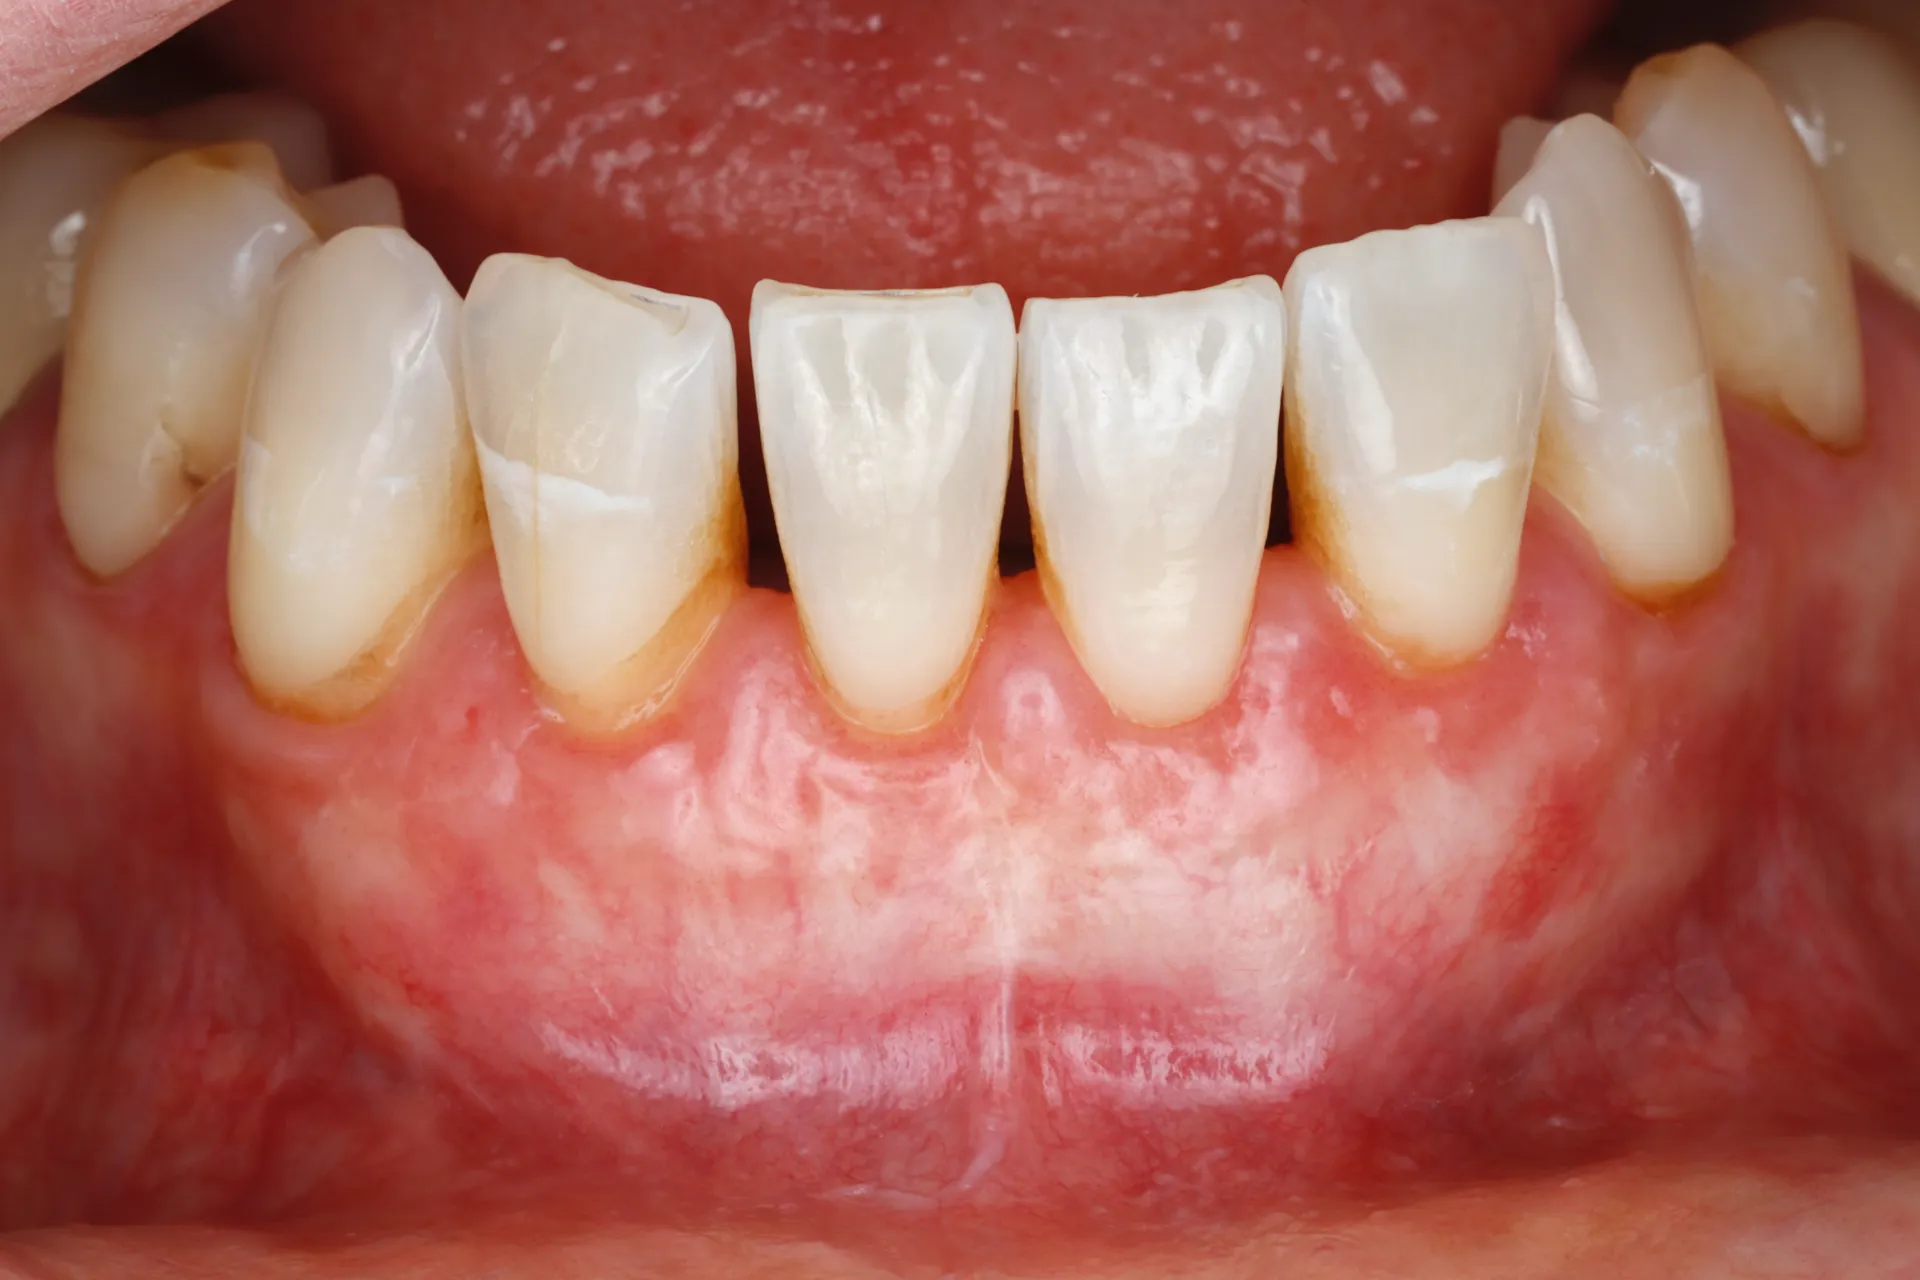

Gum Recession

Gum Grafting